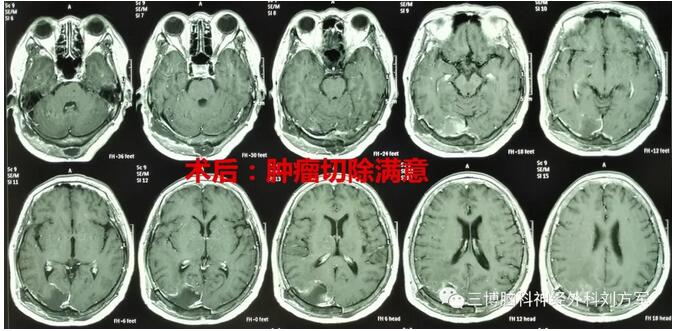

女性,68岁,头痛,视力下降,左侧肢体活动不灵活。诊断:右侧枕叶转移瘤,原发病灶为肺癌。右侧顶枕开颅肿瘤切除术。术后恢复好。病理:转移瘤。出院行放疗及化疗。ps:大的感触就是,治疗过程中,一家人面对困难,积极乐观的承担。老太太特别讲究,出院后,回当地之前,一定要到办公室和我们合影,道别!